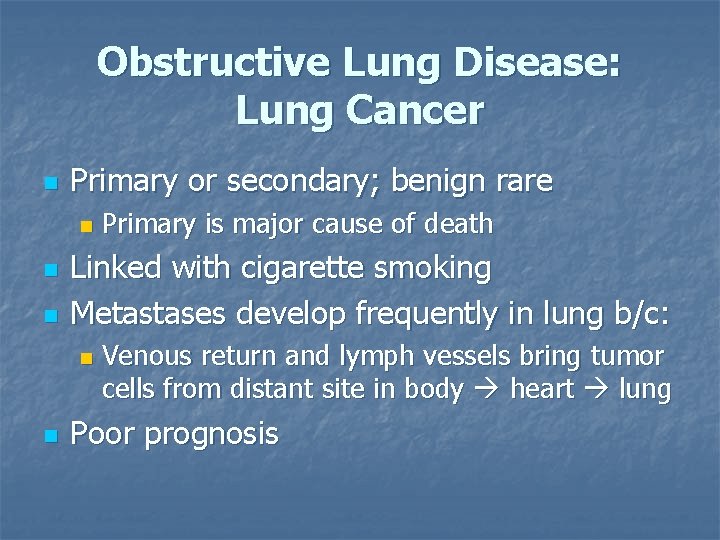

Obstructive Lung Disease: Lung Cancer n Primary or secondary; benign rare n n n Linked with cigarette smoking Metastases develop frequently in lung b/c: n n Primary is major cause of death Venous return and lymph vessels bring tumor cells from distant site in body heart lung Poor prognosis

LUNG CANCER n n Abnormal cells multiply and form malignant tumours called carcinomas Carcinomas impede healthy lung tissue – making breathing difficult

LUNG CANCER - causes n n n Carcinogens (cancercausing agents) in cigarette smoke are the leading cause of lung cancer Exposure to radon – a heavy gaseous radioactive element – found in rocks, soil and some buildings Exposure to asbestos – found in some insulation & ceiling tiles

LUNG CANCER - diagnosis n n n X-ray CT scan (computed tomography – a cross-section of the lungs is taken) Helical low-dose CT scan detect very small tumours (see right)

Lung Cancer—treatment n n n Surgery on localized lesions Chemotherapy and radiation Poor prognosis unless tumor in early stages of development